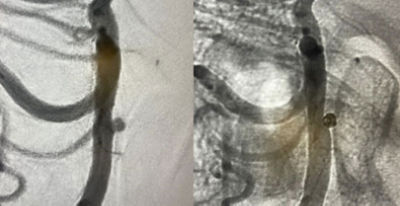

Residual ACOM aneurysm

Physician: Dr. Rahul B. Jadhav, Little Rock, AK

Aneurysm dimensions:

Height: 2.47mm

Width: 2.19mm

Neck: 2mm

Coils used:

Target Tetra 3mm x 6cm, 3mm x 4.5cm, 2.5mm x 3.5cm

“In my early cases it excelled my expectations and aced the outcome.”

– Dr. Rahul B. Jadhav